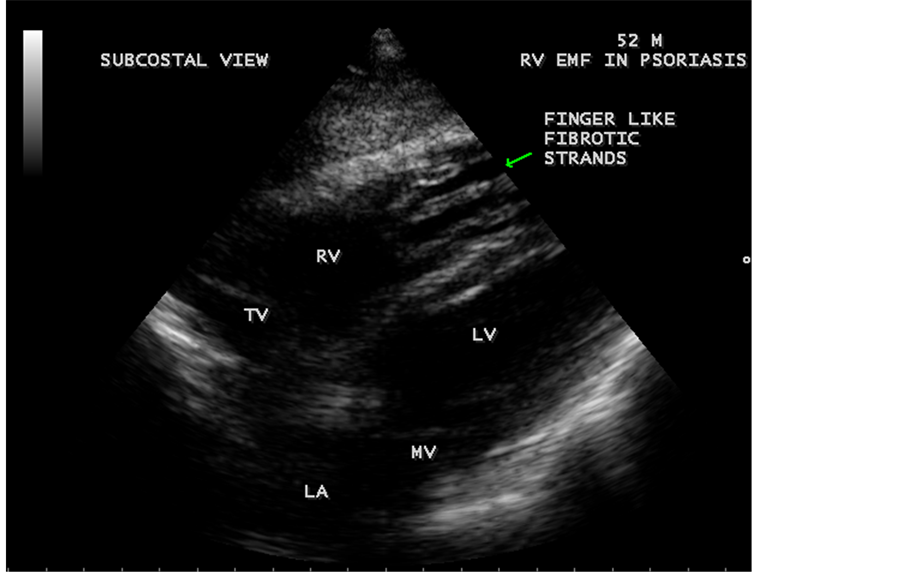

Transthoracic echocardiography revealed strong fibrous strands appearing as “finger like projections” or “cobra-head” appearance in the right ventricular apex due to fibrosis of muscular trabeculae, suggesting right ventricular endomyocardial fibrosis as shown in Figure 3 to Figure 7.

Figure 3. Subcostal view showing the “finger like” projections of fibrous strands in the RV (right ventricular) apex suggesting Right ventricular endomyocardial fibrosis in a 52-year-old male with psoriasis.

enlargement as in Figure 33 are the characteristic features of advanced stage of EMF. The fibrosed muscular trabeculae extending into the cavities from the walls of the chambers in the right ventricle visible as “cobra heads” as in Figure 4 and in pericardial sac as in Figure 29. Aneurysmal right ventricle with scattered areas of fibrosis in the sub tricuspid region and a notch in the right atrium is well seen in a 14-year-old boy as in Figure 43. Right atrial notch is frequently noticed in EMF patients as shown in Figure 42 in a 47-year-old male with left ventricular EMF and moderate pericardial effusion.